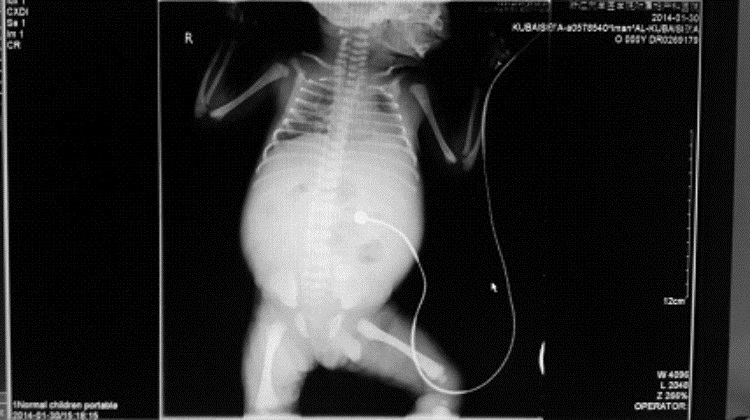

停经37+2周B超示:胎儿腹腔内12.2 cm×9.2 cm×7.2 cm液性暗区,内见分隔样回声,透声差(图 1),同日阴道分娩一男婴,Apgar评分8~9分/1~5 min,体质量2 750 g。新生儿查体:腹胀明显,腹部X线结果:腹部膨隆,两侧膈下无游离气体影,腹腔内中下腹部见不规则团片状及点状稍高密度及高密度影,最大为1.6 cm×1.2 cm,腹内显示少许肠管内有气体,未见明显气-液平面,诊断结果:腹腔囊肿,畸胎瘤?(图 2)。初步诊断:先天性腹腔囊肿,需手术治疗转入浙江大学医学院附属儿童医院。

图 2 新生儿腹部X线结果